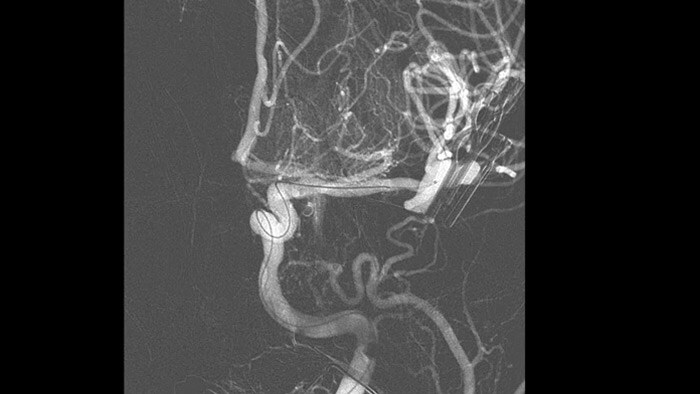

SmartCT Angio ist eine Röntgen-Erfassungstechnik, die eine vollständige, hochauflösende 3D-Darstellung der zerebralen Gefäße aus einem einzigen Rotationsangiographielauf erstellt. Sämtliche Funktionen werden dabei über den Touchscreen am Tisch gesteuert. Dies kann die Sichtbarkeit stark gewundener oder komplexer Anatomien verbessern, die auf einem 2D- oder DSA-Bild möglicherweise nicht zu sehen sind.

SmartCT Angio liefert in wenigen Sekunden eine volumetrische Darstellung und unterstützt so die Beurteilung von Position, Größe, Hals und Schweregrad des Aneurysmas für die Behandlungsplanung. Die 3D-Volumina werden mit hoher räumlicher Auflösung und automatischer Bewegungskompensation dargestellt.

SmartCT Vaso verbessert die Darstellung endovaskulärer Stents, Flow Diverter und anderer Instrumente sowie der Gefäßmorphologie bis auf Perforatorebene. Diese Erfassungstechnik basiert auf einem Cone-Beam-CT-Scan in Kombination mit einer intraarteriellen Kontrastmittelinjektion. Sie wird zunehmend zur Nachkontrolle von mit Flow-Diverter-Stents behandelten Aneurysmen verwendet, um die Positionierung des Implantats zu überprüfen.

ClarityIQ senkt die Patientendosis von Neuro-DSA*-Verfahren bei gleichbleibender Bildqualität um 75 % gegenüber Systemen ohne ClarityIQ und ist so für eine breite Patientenpopulation geeignet. Die automatische Bewegungskompensation von ClarityIQ entfernt Schädel- und Bewegungsartefakte, was bei der Platzierung kleiner Implantate an der Schädelbasis entscheidend ist.